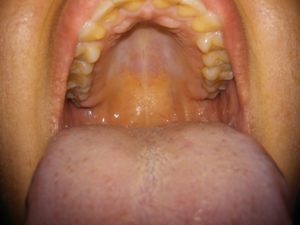

Сиалометаплазия

Это доброкачественное поражение слюнных желёз на нёбе. Первыми симптомами являются небольшие уплотнения в виде узелков на твёрдой части нёба. Воспалённые участки быстро увеличиваются в размерах и могут достигать около 2 см. При этом человек испытывает ноющую боль и чувство пульсации в месте локализации образований язв.

Заболевание встречается в ротовой полости взрослых людей в возрасте 40–50 лет. Статистика указывает, что мужчины страдают этим недугом чаще, чем женщины. Причиной болезни может послужить травма слизистой, спазм сосудов или вследствие инъекций во время стоматологических процедур.

Правильная постановка диагноза здесь играет решающую роль, так как общую боль в полости рта могут вызывать различные заболевания, у которых имеются схожие симптомы.